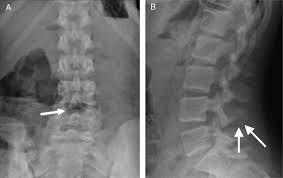

2. Radiografía

1. Escoliosis, fracturas, osteofitos, tejidos blandos